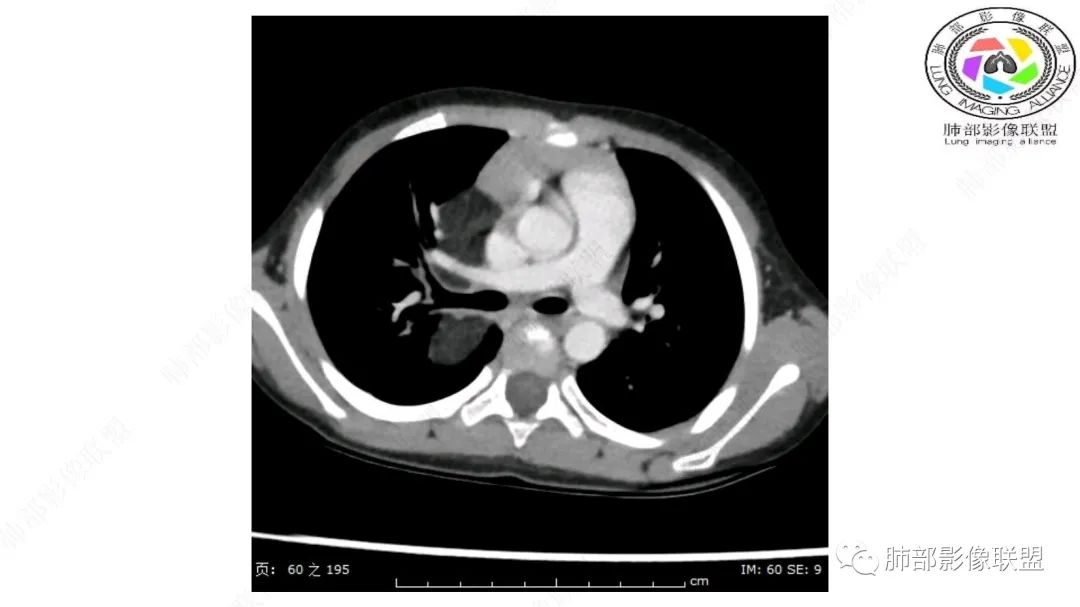

右上纵隔混杂密度肿块,边缘光整,与纵隔分界清,其内多发脂肪密度,增强无明显强化,其内血管穿行,考虑纵隔脂肪母细胞瘤,鉴别畸胎瘤,脂肪肉瘤。

右纵隔团状,密度不均,脂肪密度为主,内可见腺体样组织,类似乳腺,病灶边缘有分叶,与胸腺关系密切,增强后血管穿行。考虑胸腺脂肪瘤(不典型垂乳征),鉴别畸胎瘤。

三岁小儿,右侧纵隔巨大脂肪密度肿块,肺动脉穿行其中,密度欠均匀,未见明确实性成分,纵隔脂肪母细胞瘤,冬眠瘤鉴别纵隔脂肪增多症(多弥漫对称)。

可以看到造影剂进入的丛状结构

密度不均,非纯脂肪成分。斑片状密度略高区域有轻度填充式强化。

婴幼儿,病变较大,跨肺门,分叶,富含纤维或黏液、含成熟脂肪,破坏力弱或无,浸润性生长模式不明显,未见远处转移。

综合:富含成熟脂肪的、可以有丛状结构的,可以有纤维或黏液的良性或低度恶性肿瘤。常见疾病谱:脂肪瘤、神经纤维瘤样错构瘤、冬眠瘤、血管脂肪瘤、髓脂肪瘤、脂肪母细胞瘤、黏液样脂肪肉瘤。

病灶属于交界区,主体位于肺内,占位效应明显,前方突入胸壁,胸腺受压变形,胸膜显示欠清楚;病灶包绕上叶肺动脉;似乎有体动脉供血。符合肺内的点:包绕上叶肺动脉分支;符合纵隔的点:前方似乎突入胸壁,与胸腺关系比较密切,但是与上腔静脉的关系提示病灶不支持纵隔来源,前纵隔的常规会将上腔静脉受压后移、外移,这是不符合的。

2.肺动脉穿行也许是肺内来源最重要支持点!

脂肪母细胞瘤由成熟程度不同的脂肪组织、纤维间隔、黏液基质、小血管丛等间质成分组成,以脂肪组织与黏液样基质为主,其影像学表现取决于上述组织成分。典型的CT和MRI表现为:前后纵隔均可发生,常见于前纵隔;肿块大小不一,直径多在3cm~7cm,密度均匀,CT值呈水样或脂肪密度,脂肪组织密度或信号为主的肿块,其内密度或信号不均匀,可见粗细不一的分隔影,且有结节、片状影,后者可呈轻中度强化;结节状肿瘤包膜完整;弥漫性者包膜不明显,常呈浸润性生长;周围结构为受压和推移改变,可有少量胸腔积液,淋巴结无增大。